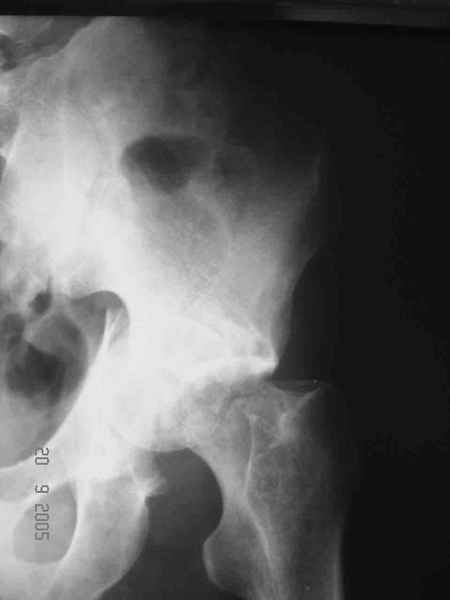

Re: Перелом acetabulum и проксимального отдела бед

Привет! Вот недавно прооперировали похожий на ваш случай - впадина + шейка (правда у нас впадина поперечный+задний край). После травмы прошло 4 недели. мужчине 46 лет. С такой комбинацией все показания к первичному протезированию. Морально и технически мы к этому уже созрели.Но больной не собрал денег на протез. Выполнили остеосинтез впадины и шейки, прекрасно понимая, что головка вскоре рассосется, мы хотя бы надемся что к этому времени таз срастется, как говорится создали все условия для дальнейшего протезирования (может, и протез в последующем подешевле будет, в смысле, без укрепляющего кольца?). Привет Рункову!

Привет Алекей! Сделано неплохо, поздравляю, хотя второй винтик можно было бы и подлиннее в шейку загнать! Пара вопроов: доступ такой же? головка была свободной или висела на капсуле?

Согласен, можно было и подлиннее. Доступ такой же - чрезвертельный, только разрез кожи прямой (а не Y, чего то я разницы не ощущаю). Головка была абсолютно свободной (то есть во время остеосинтеза таза лежала в стакане и не мешалась). Шансов, что она прирастет 0,00001%. Хотели даже выбросить, но привинтили как временный биологический протез (читай свободный трансплантат), чтоб на период срастания таза бедро проксимально не ушло (может ортопеды потом спасибо скажут). Ну а у вас первичное протезирование при переломе впадины тоже пока полько в планах?